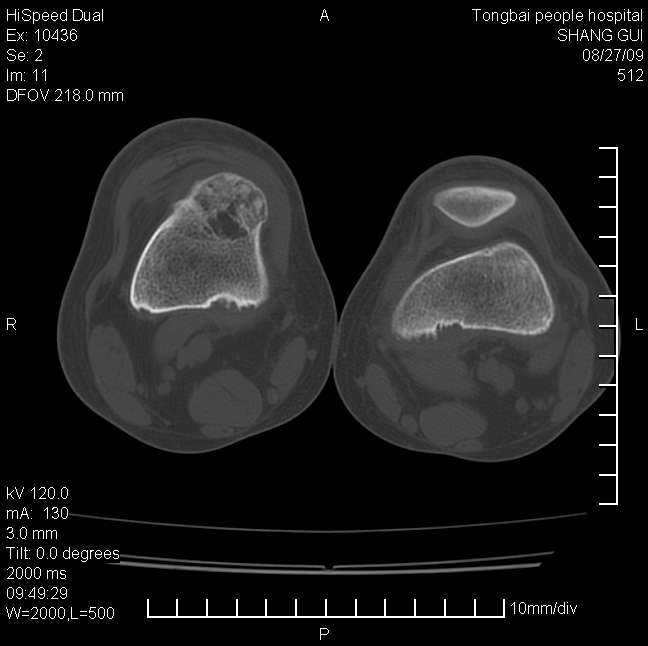

女,12岁。无意发现股骨下端隆起。局部皮肤颜色,温度无异常。

考虑右股骨下端骨纤维结构不良;不排除非骨化性纤维瘤。

不能排除,其实平片更直观。宽基底骨软骨瘤皮质与骨干皮质相连,髓腔与髓腔相通,骨纹理走行方向一致,部分软骨帽可有钙化,本例病变内“磨玻璃状、多囊状改变”比较符合骨纤。